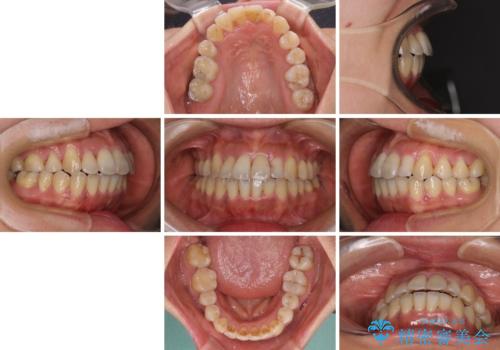

狭い上顎骨を拡大 著しい叢生を抜歯矯正で改善

骨格的に上顎は狭く、下顎は右側にシフトしていたため、右側臼歯はクロスバイトとなっていました。

上顎骨を急速拡大装置により拡大し、ワイヤー装置による抜歯矯正治療を行うこととしました。

治療途中、長期間海外旅行をされたり、帰国後には遠方へ転居されたりと、治療期間が伸びましたが、2年強で治療を終えることができました。